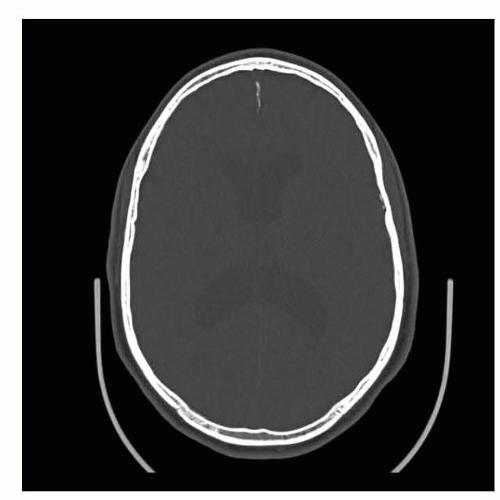

IMAGING AND OTHER DIAGNOSTIC STUDIES

Preoperative evaluation should include a CT scan to assess the thickness of the parietal bones for harvesting grafts and of any potential midline abnormalities.

Younger patients may lack a true diploic architecture (FIG 2), whereas older patients may have areas of thin calvarial bone.